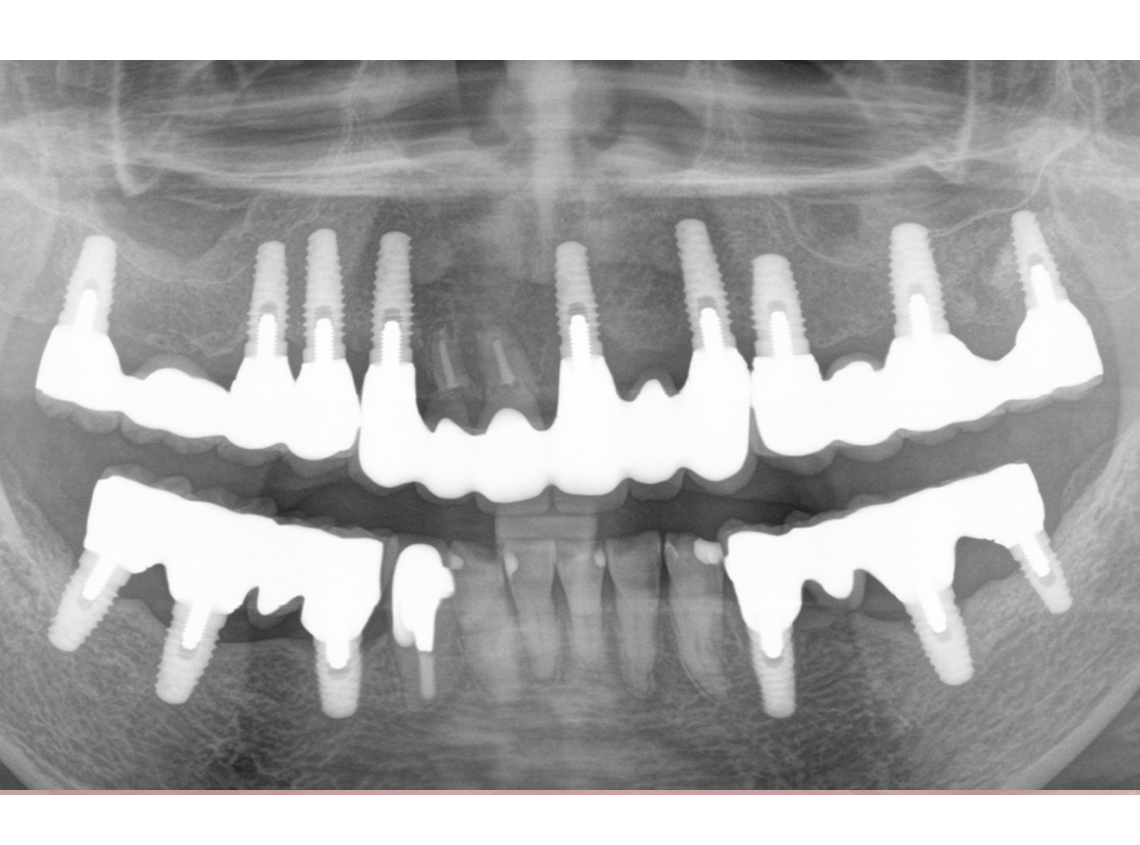

4.最終補綴物装着(2008年)

5.術後14年経過(2022年)

2008年8月27日撮影

インプラント埋入部の骨レベルは埋入時と変わらず、患者様ご自身のメンテナンスも良好で、経過は非常に良く、満足されています。